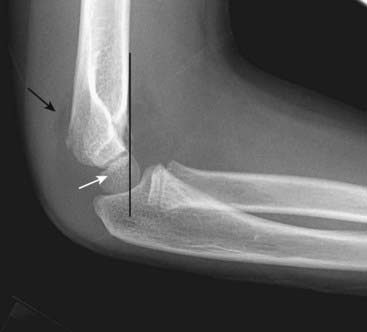

Figure 22-28 Supracondylar fracture.

A supracondylar fracture of the distal humerus is a common fracture in children, and its findings may be subtle. Most of these fractures produce posterior displacement of the capitellum of the distal humerus. On a true lateral film, the anterior humeral line (a line drawn tangential to the anterior humeral cortex and shown here in black) should bisect the middle portion of the capitellum (solid white arrow). When there is a supracondylar fracture, this line will pass more anteriorly, as it does here. There is a positive posterior fat pad sign present (solid black arrow).